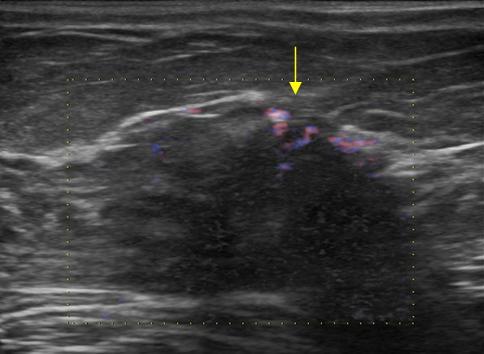

Ung thư vú

» Thông tin: Nữ giới – 76 tuổi.

» Lâm sàng: Khối tuyến vú.